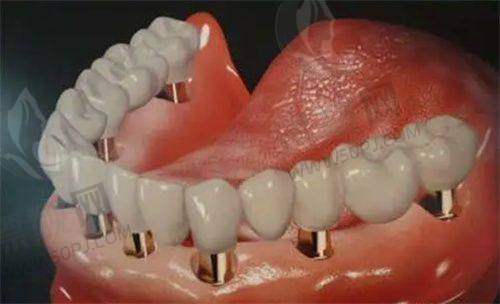

二、设备精良不打折,“拿得出手”的技术不是空谈

现在口腔诊疗讲究一个字:精!而瑞兴口腔医院引进了多种进口高端诊疗设备,比如数字化3D种植导航、口腔CT、显微镜种牙、德国西诺德牙椅等。别小看这些“电动玩具”,确实改变了过去只靠眼就是干的时代,精度高、创伤小、修复快,还能事前3D建模、精密植入,真正做到”种牙不靠瞎蒙,全靠导航定位”。要知道,在上海要配齐这些设备的私立医院,可没几家。

3D口腔CT | 三维成像,精细诊断病灶 | 减少误诊风险,提高种植成功几率 |

数字导板种植 | 精细设计植体位置 | 创口小、修复快,避免二次手术 |